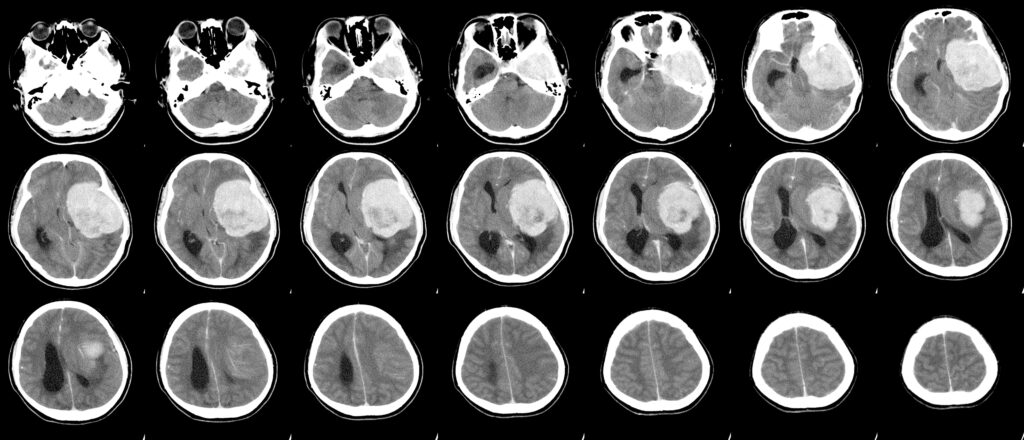

California Woman Sues Pfizer for Brain Tumor Allegedly Resulting From Depo-Provera Contraceptive Shots Posted: December 10, 2024 Levin Papantonio (LP) law firm has filed a lawsuit on behalf of Alicia Wilson, a resident of Upland, San Bernardino, California, against Pfizer, Inc.; Viatris, Inc.; Greenstone, LLC; Pharmacia and Upjohn Company LLC; Pharmacia, LLC; and Prasco LLC. The complaint (Civil Action No.: 5:24-cv-02524) alleges that the defendants manufactured, promoted, and sold the prescription drug Depo-Provera without adequately warning of its connection to the development of meningiomas, a type of brain tumor that can have severe and life-altering effects on patients. Wilson was diagnosed with an intracranial meningioma. A craniotomy confirmed her tumor was a Grade 1 meningioma. The lawsuit asserts that this serious condition, as well as its treatment and long-term consequences, has caused her severe health challenges, emotional distress, and the inability to work. Wilson first became aware of the connection between her tumor and her use of Depo-Provera in September 2024. “Depo-Provera users like Alicia Wilson placed their trust in these companies, only to face devastating consequences due to the lack of adequate warnings.”Chris Paulos, Attorney, Levin Papantonio The complaint highlights decades of scientific research indicating that Depo-Provera, when prescribed and used as directed, significantly increases the risk of intracranial meningioma. Studies have demonstrated that progesterone, its synthetic counterpart progestin, and specifically Depo-Provera, can cause or contribute to the development of these brain tumors. Despite this evidence, the U.S. label for Depo-Provera fails to disclose the increased risk of intracranial meningiomas, the lawsuit claims. Moreover, the defendants allegedly neglected to adequately warn users and prescribers in the United States about the associated dangers or the need for monitoring for related symptoms. “Depo-Provera users like Alicia Wilson placed their trust in these companies, only to face devastating consequences due to the lack of adequate warnings,” said Levin Papantonio attorney Chris Paulos. “This lawsuit seeks to hold these manufacturers accountable for the harm caused by their failure to inform patients and medical providers about the drug’s risks.” As a result of the defendants’ conduct, Wilson has endured invasive brain surgery, ongoing medical surveillance, and severe physical and emotional harm. The lawsuit demands compensatory damages, statutory damages, punitive damages, and other relief, including attorneys’ fees and pre- and post-judgment interest. Attorneys Want to Consolidate Depo-Provera Cases More than 20 lawsuits have been filed against the manufacturers of the injectable contraceptive Depo-Provera, prompting a request for case coordination in the Northern District of California. A motion filed with the U.S. Judicial Panel on Multidistrict Litigation seeks to consolidate these cases before U.S. District Judges William Orrick III or Jon Tigar. The motion highlights that most plaintiffs are likely to be from California or Massachusetts, where innovator liability laws permit lawsuits against brand manufacturer Pfizer Inc. even if the plaintiffs used unauthorized generic versions of the drug. The filing references 22 active cases against Pfizer and authorized generic providers, with 18 of those cases in California, including six in the Northern District. Additional cases are pending in Indiana, Massachusetts, Missouri, and Nevada. With nearly 2 million American women having used Depo-Provera, attorneys anticipate filing thousands of similar lawsuits, emphasizing the need for streamlined proceedings through multidistrict litigation. Depo-Provera Is a Hot Topic in the Legal Community In October, Paulos delivered a presentation at MTMP in Las Vegas, updating thousands of mass tort lawyers on the Depo-Provera litigation. The conference session provided crucial insights and underscored the importance of holding pharmaceutical companies accountable for harm caused by the popular contraceptive drug. “…it appears Upjohn targeted a demographic that likely consisted largely of black, unmarried women who already had one child but could not afford to raise more children.”Chelsie Green, Attorney, Levin Papantonio Levin Papantonio Attorney Chelsie Green has written an article on Depo-Provera for the Florida Justice Association (FJA). The piece will be published in the January/February issue of the FJA Journal. In the article, Green delves into the origins of Depo-Provera and the FDA’s approval process for the drug. This includes disturbing clinical trials in the ’60s at Atlanta’s Grady Memorial Hospital Family Planning Clinic. “The shoddy nature of this clinical study precludes us from knowing for certain, but based on what we do know, it appears Upjohn targeted a demographic that likely consisted largely of black, unmarried women who already had one child but could not afford to raise more children.” Green said. “This would be an easy way to hook women into participating in the study. And it probably helped Upjohn sleep better at night after failing to inform these women of the risks of using this drug.”